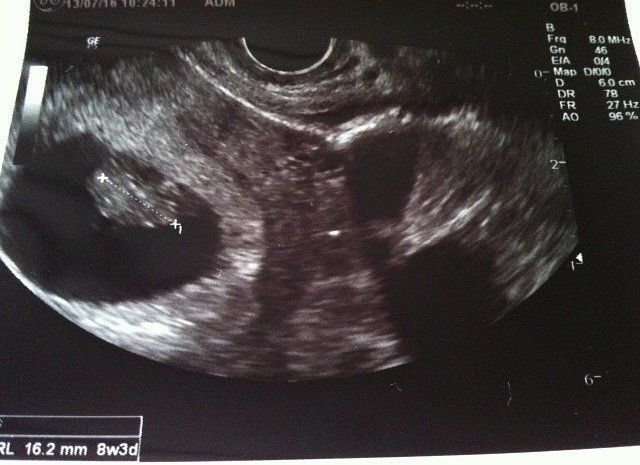

Tomomiさんの妊娠8週目のエコー写真 ついに産婦人科へ転院

妊娠3カ月目に突入し、初めての産婦人科へ。里帰りまでの約半年お世話になりました。

初めて心音を聞かせてもらい、震えるほど感動しました。「ドクドクざわざわ」、一生懸命生きている命の音を聞き、「ママもしっかりしなくちゃ」と背筋が伸びました。

母子手帳交付の許可も降り、4年目の結婚記念日に最高のプレゼントを貰いました。